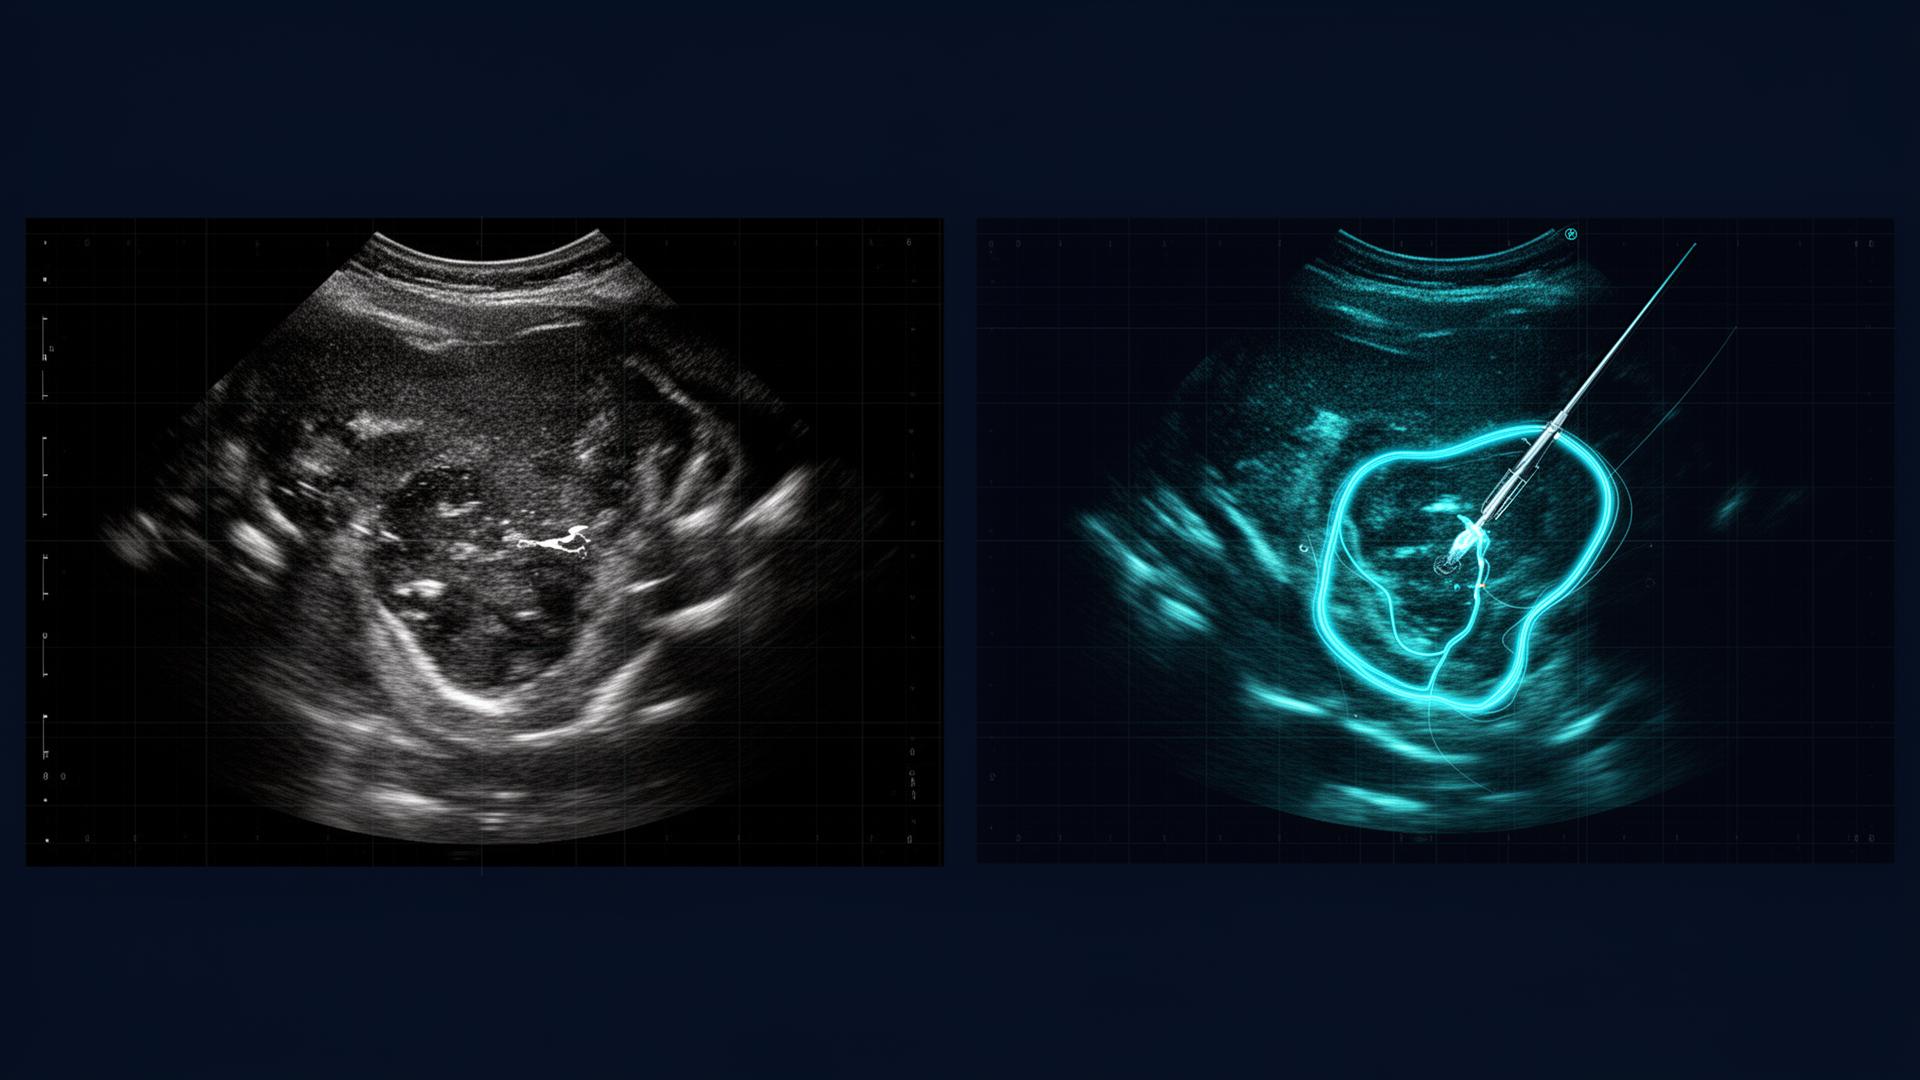

Real-time dual-target tracking using Optovance's multi-modal foundation model

Segmentation playground for trajectory prediction and interventional procedures with sub-mm accuracy.